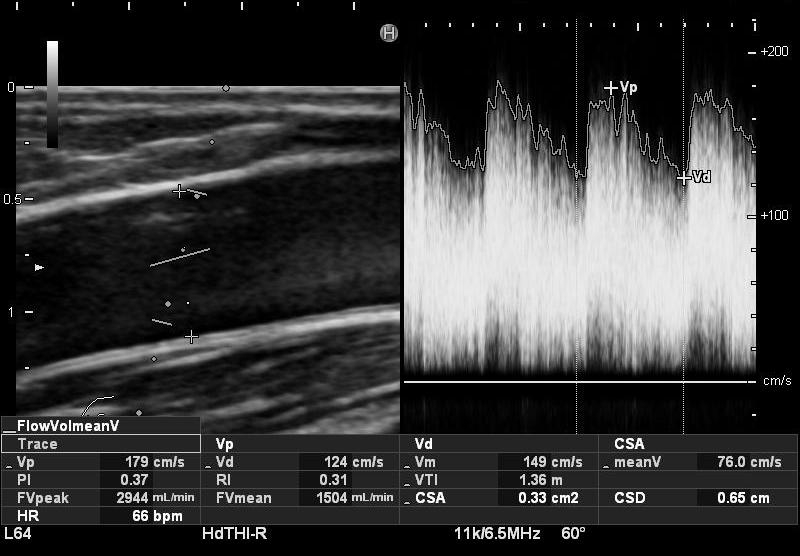

・上腕動脈血流量・RI

上腕動脈血流量・RIの測定については、基本的には上腕中間部と肘部の2ヵ所の上腕動脈で測定し、血流量に関しては、過大評価とならないよう、mean traceにより算出されるFv mean(平均流速における特定範囲の平均値)を参考にしています。

※上腕動脈血流:300~350ml/min以上、RI:0.6~0.7以下をカットオフ値とし、透析中の脱血の状態等も考慮し、必要に応じ血管外科等の受診を検討しています。